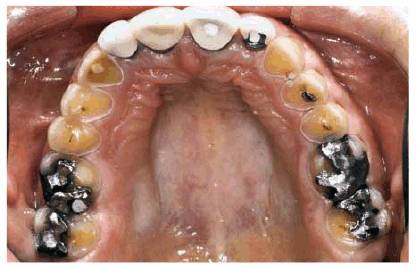

patient (Figures 17-1A to

C

Figure 17-1A to C: These photographs illustrate the complex dental condition of a 71-year-old male: (A) The palatal cervical regions of the maxillary anterior teeth exhibit sharp, wedge-like lesions that are characteristic of abfraction. These areas would be difficult, if not impossible, to have resulted from toothbrush abrasion. (B) The buccal aspects of the maxillary posterior teeth show smooth, concave configurations that are consistent with toothbrush abrasion and/or erosion. (C) The buccal surfaces of the mandibular teeth have lesions that possess components of both abfraction (sharp margins in the occlusal regions) and abrasion (concave geometry and gingival recession in the cervical regions).